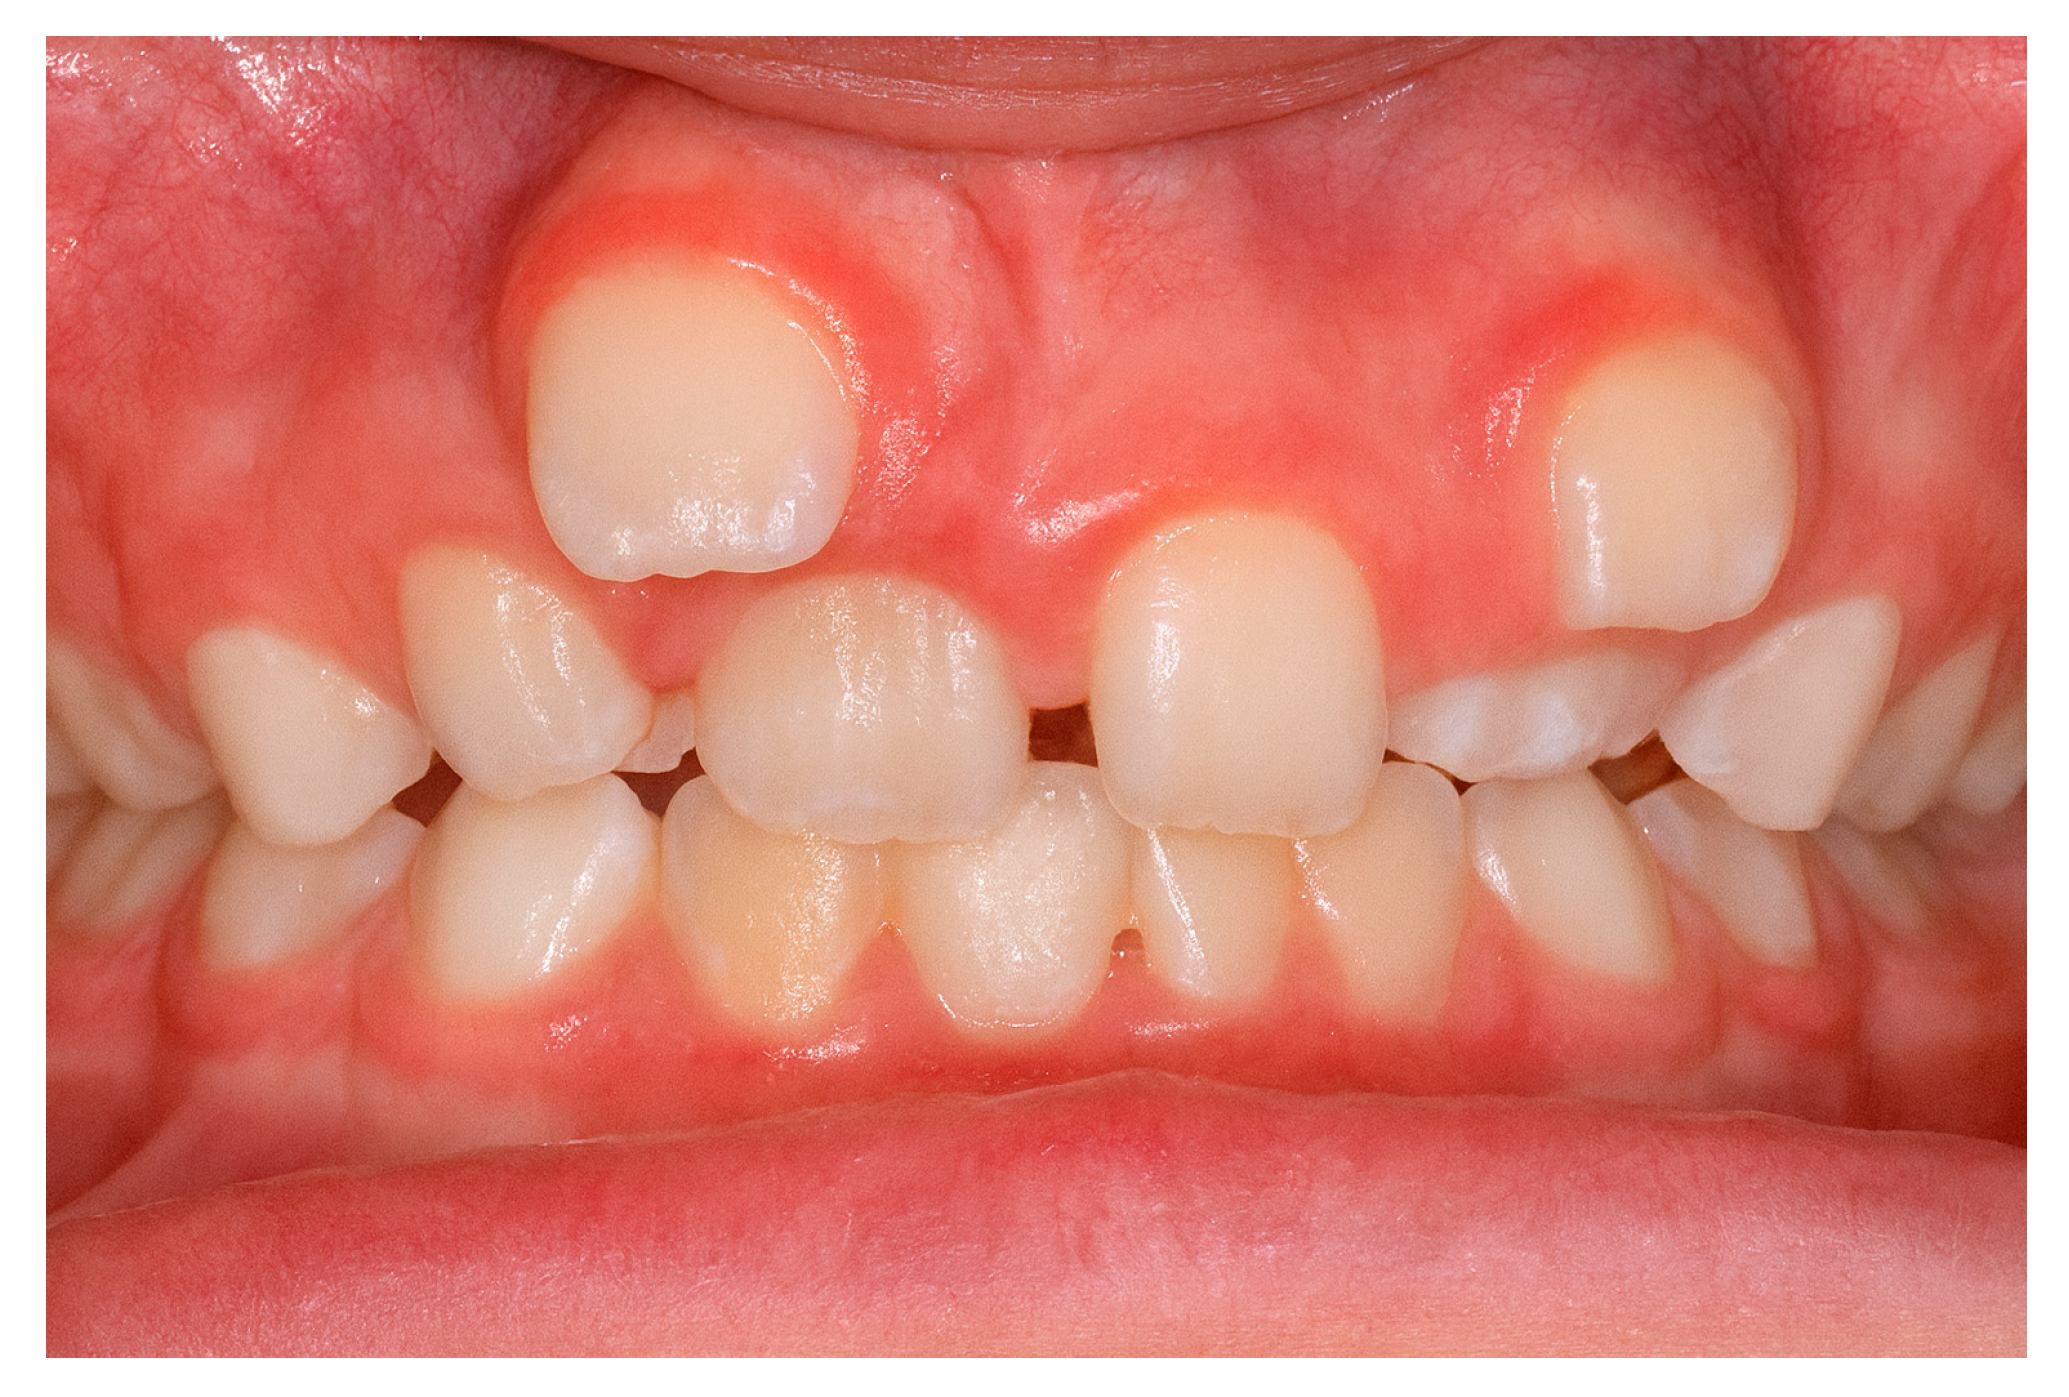

Accurate diagnosis and precise localization are indispensable for successful treatment planning and prevention of secondary complications [2,18]. Traditional two-dimensional radiographic methods [33], such as panoramic (orthopantomogram) and periapical radiographs (Figure 3), remain valuable as initial diagnostic tools; however, they often fail to provide sufficient information regarding the three-dimensional relationship between the ST and adjacent anatomical structures [33,34].

Figure 3. Orthopantomogram showing a supernumerary tooth located between the left mandibular canine (tooth 3.3) and the left mandibular first premolar (tooth 3.4).